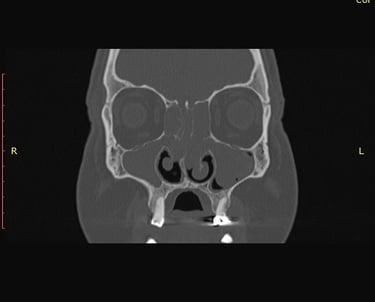

Problemi sa sinusima spadaju među najčešće kronične tegobe današnjice. Dugotrajna začepljenost nosa, glavobolje, smanjen osjet mirisa i ponavljajuće upale značajno narušavaju kvalitetu života. Dok većina pacijenata dobro reagira na konzervativnu terapiju (lijekove, ispiranja, sprejeve), kod određenog broja simptomi se uporno vraćaju. Tada se postavlja pitanje – je li vrijeme za operaciju?

Upravo tu dolazi endoskopska kirurgija sinusa (FESS – Functional Endoscopic Sinus Surgery), metoda koja je posljednjih desetljeća potpuno promijenila liječenje bolesti sinusa.

Kada je vrijeme za operaciju sinusa?

1. Kronični sinusitis (više od 12 tjedana simptoma)

2. Ponavljajuće akutne upale (više puta godišnje unatoč terapiji)

3. Nosni polipi koji uzrokuju smanjen njuh i začepljen nos

4. Komplikacije (upale oka, orbitalni apsces, širenje upale)

5. Loša kvaliteta života (nesanica, hrkanje, stalni umor, glavobolje)